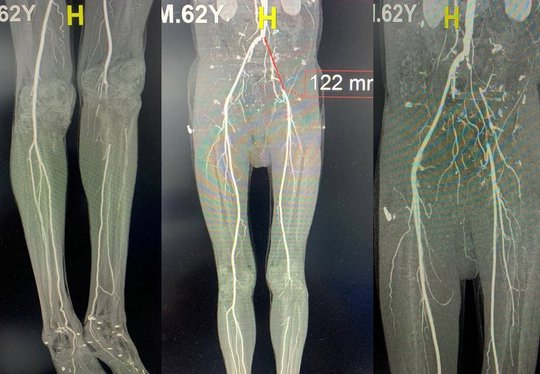

Bệnh viện đa khoa tỉnh Bắc Giang cho biết các bác sĩ vừa điều trị bảo tồn hoạt động chân trái cho bệnh nhân P.V.T., 62 tuổi, (ở Hiệp Hòa, Bắc Giang) bị hẹp tắc động mạch chi dưới mãn tính bằng phương pháp phẫu thuật bắc cầu động mạch đùi.

Bệnh nhân nhập viện trong tình trạng đau cẳng chân trái, tê bì nhiều, da khô, tái lạnh, đau nhiều và bầm tím bàn chân, ngón chân khi đi lại. Theo người nhà, bệnh nhân có tiền sử hút thuốc lá nhiều năm và đã phát hiện tắc động mạch chậu đùi trái cách đây hơn 1 năm. Gần đây, chân bệnh nhân có dấu hiệu đau nhiều, cứ đi lại vài bước là đau, ngồi thì đỡ nên đã đi khám.

Kết quả siêu âm doppler mạch máu phát hiện bệnh nhân tắc động mạch chậu đùi trái, tắc động mạch khoeo chân trái, khả năng cấp máu bàn chân trái giảm nặng. Bệnh nhân có chỉ định phẫu thuật bắc cầu động mạch đùi- đùi bằng đoạn mạch nhân tạo, mở động mạch khoeo lấy huyết khối.

Sau mổ sức khỏe bệnh nhân được cải thiện, hết cảm giác tê, sờ bàn chân, ngón chân ấm, mạch chân trái bắt rõ hơn, tình trạng tưới máu cẳng bàn chân trái được lưu thông.